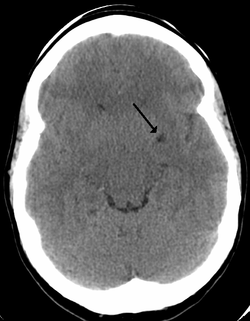

Axial fat suppressed T2 weighted MRI image in the same patient as above demonstrating extensive dilated Type 2 perivascular spaces in the right hemisphere